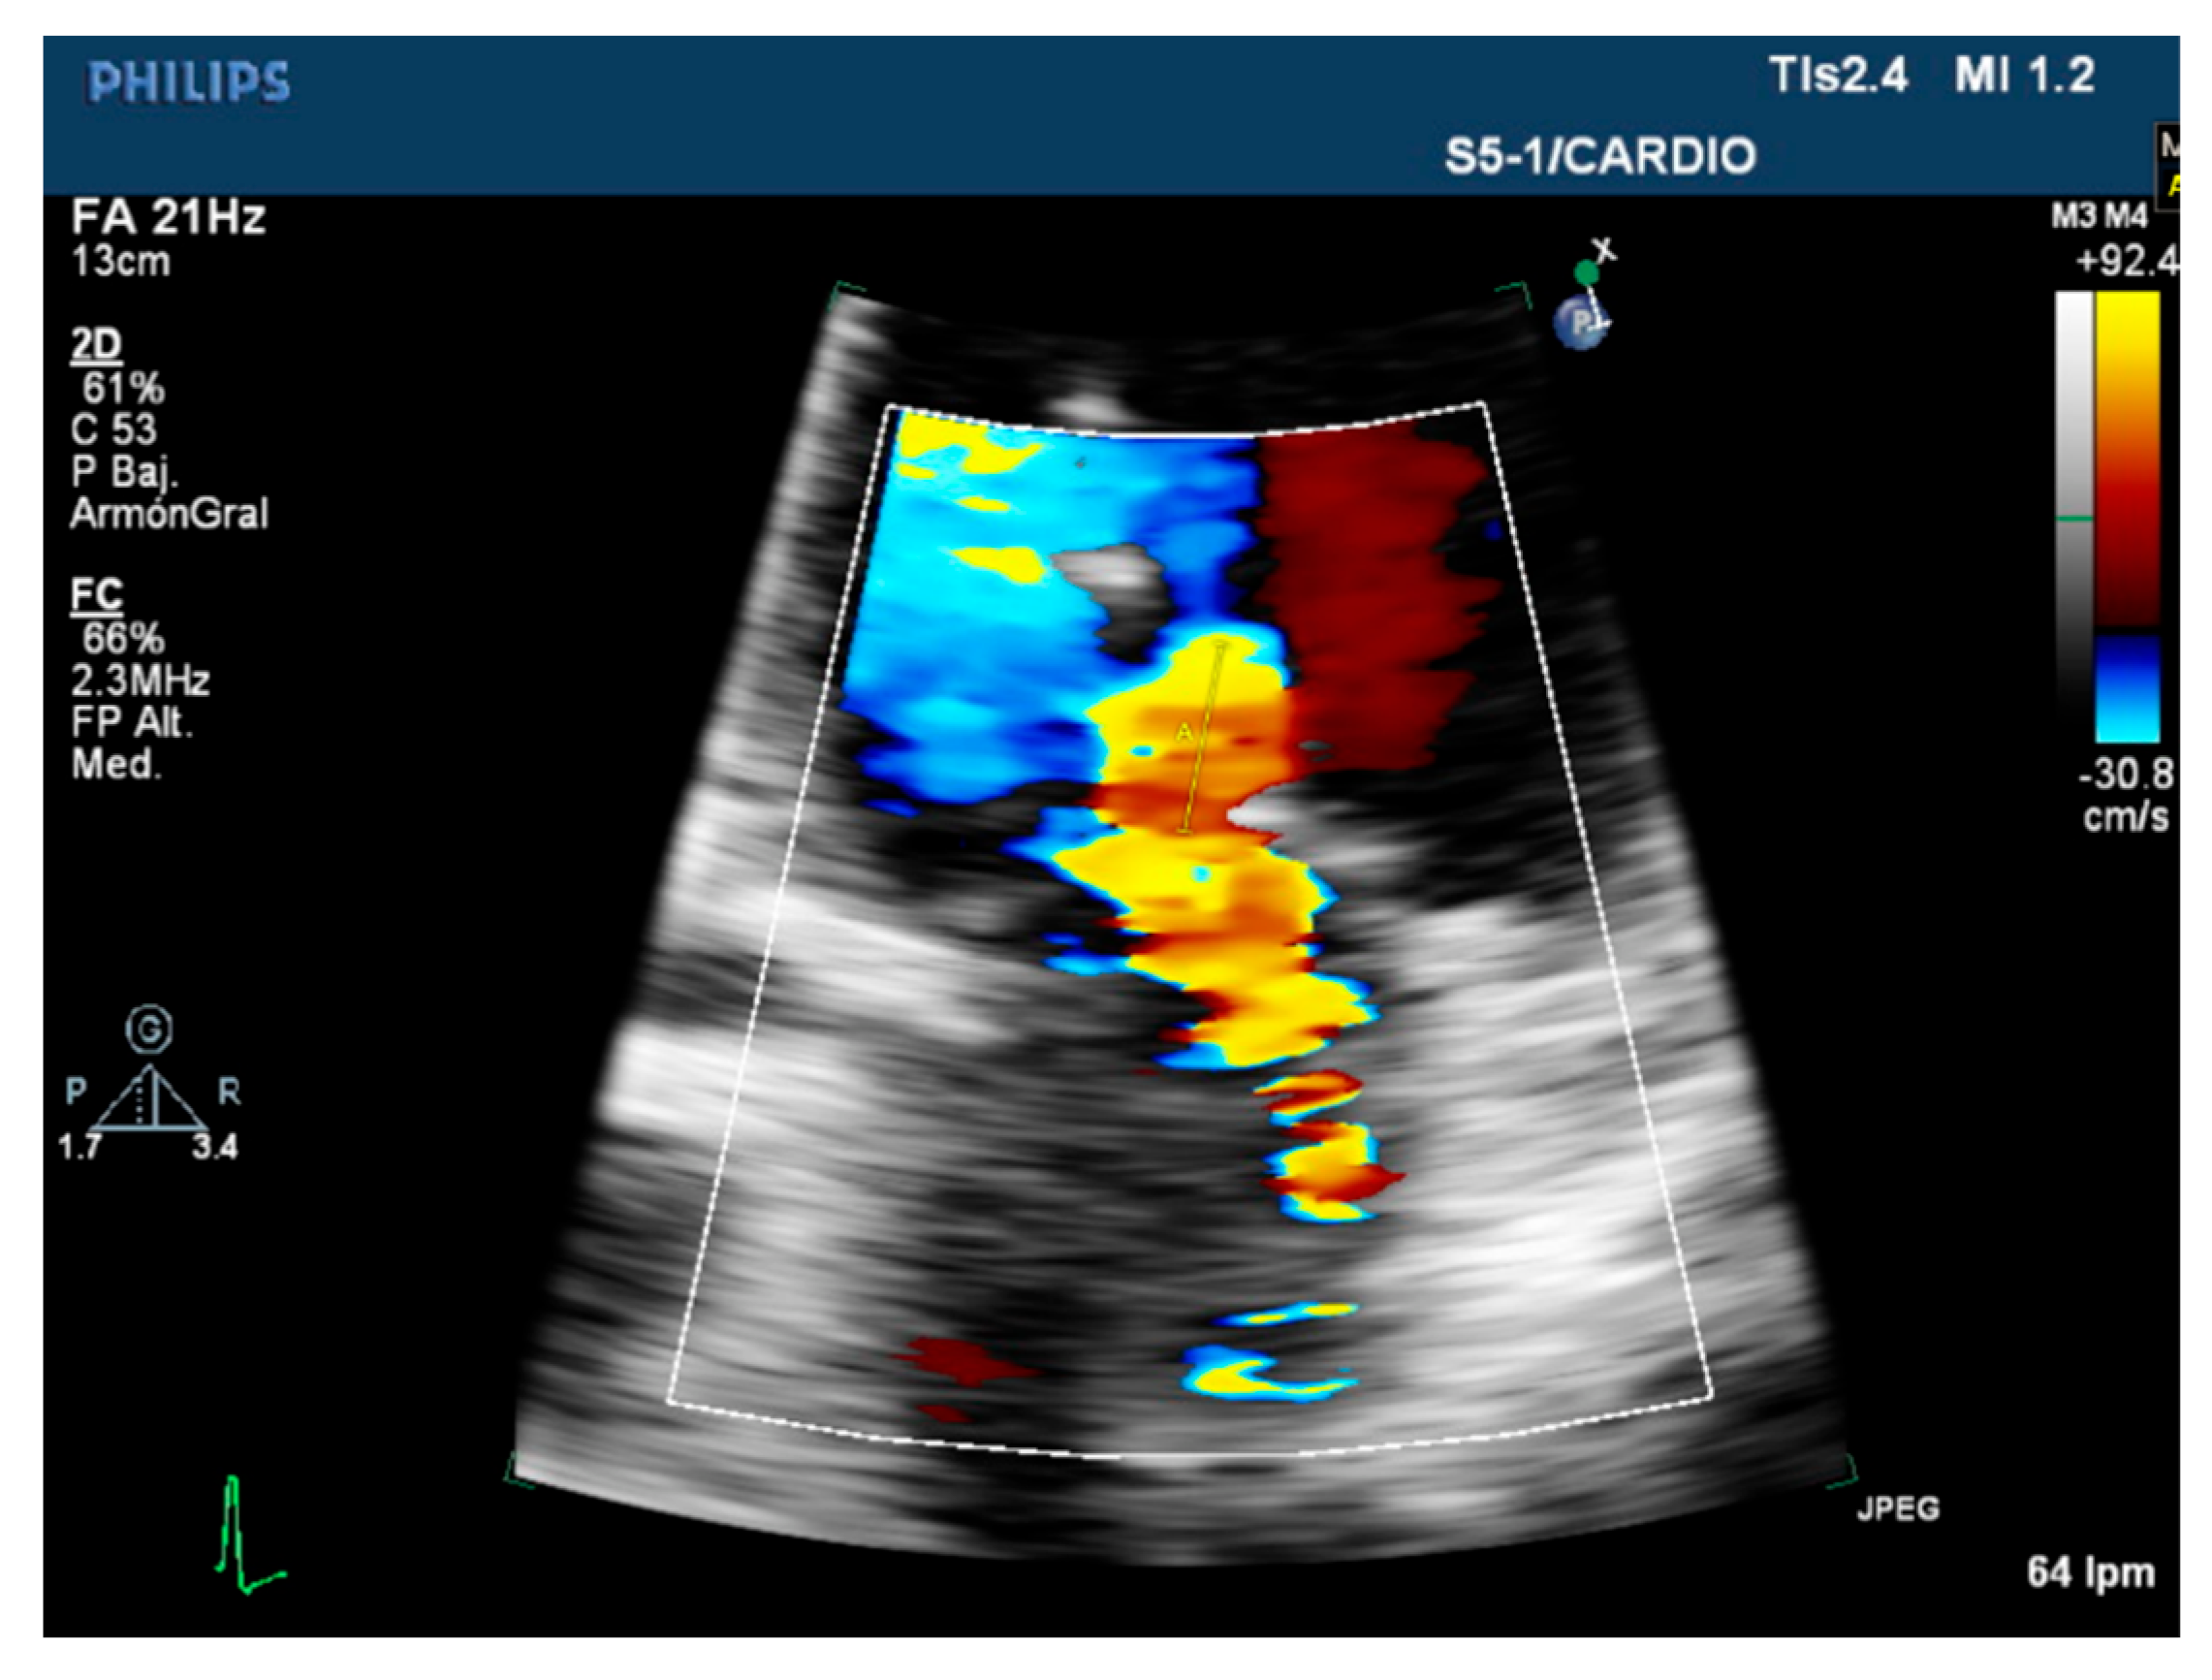

| Color flow jet | Qualitative. | Small, central. | Large central jet or eccentric reaching the posterior LA wall. |